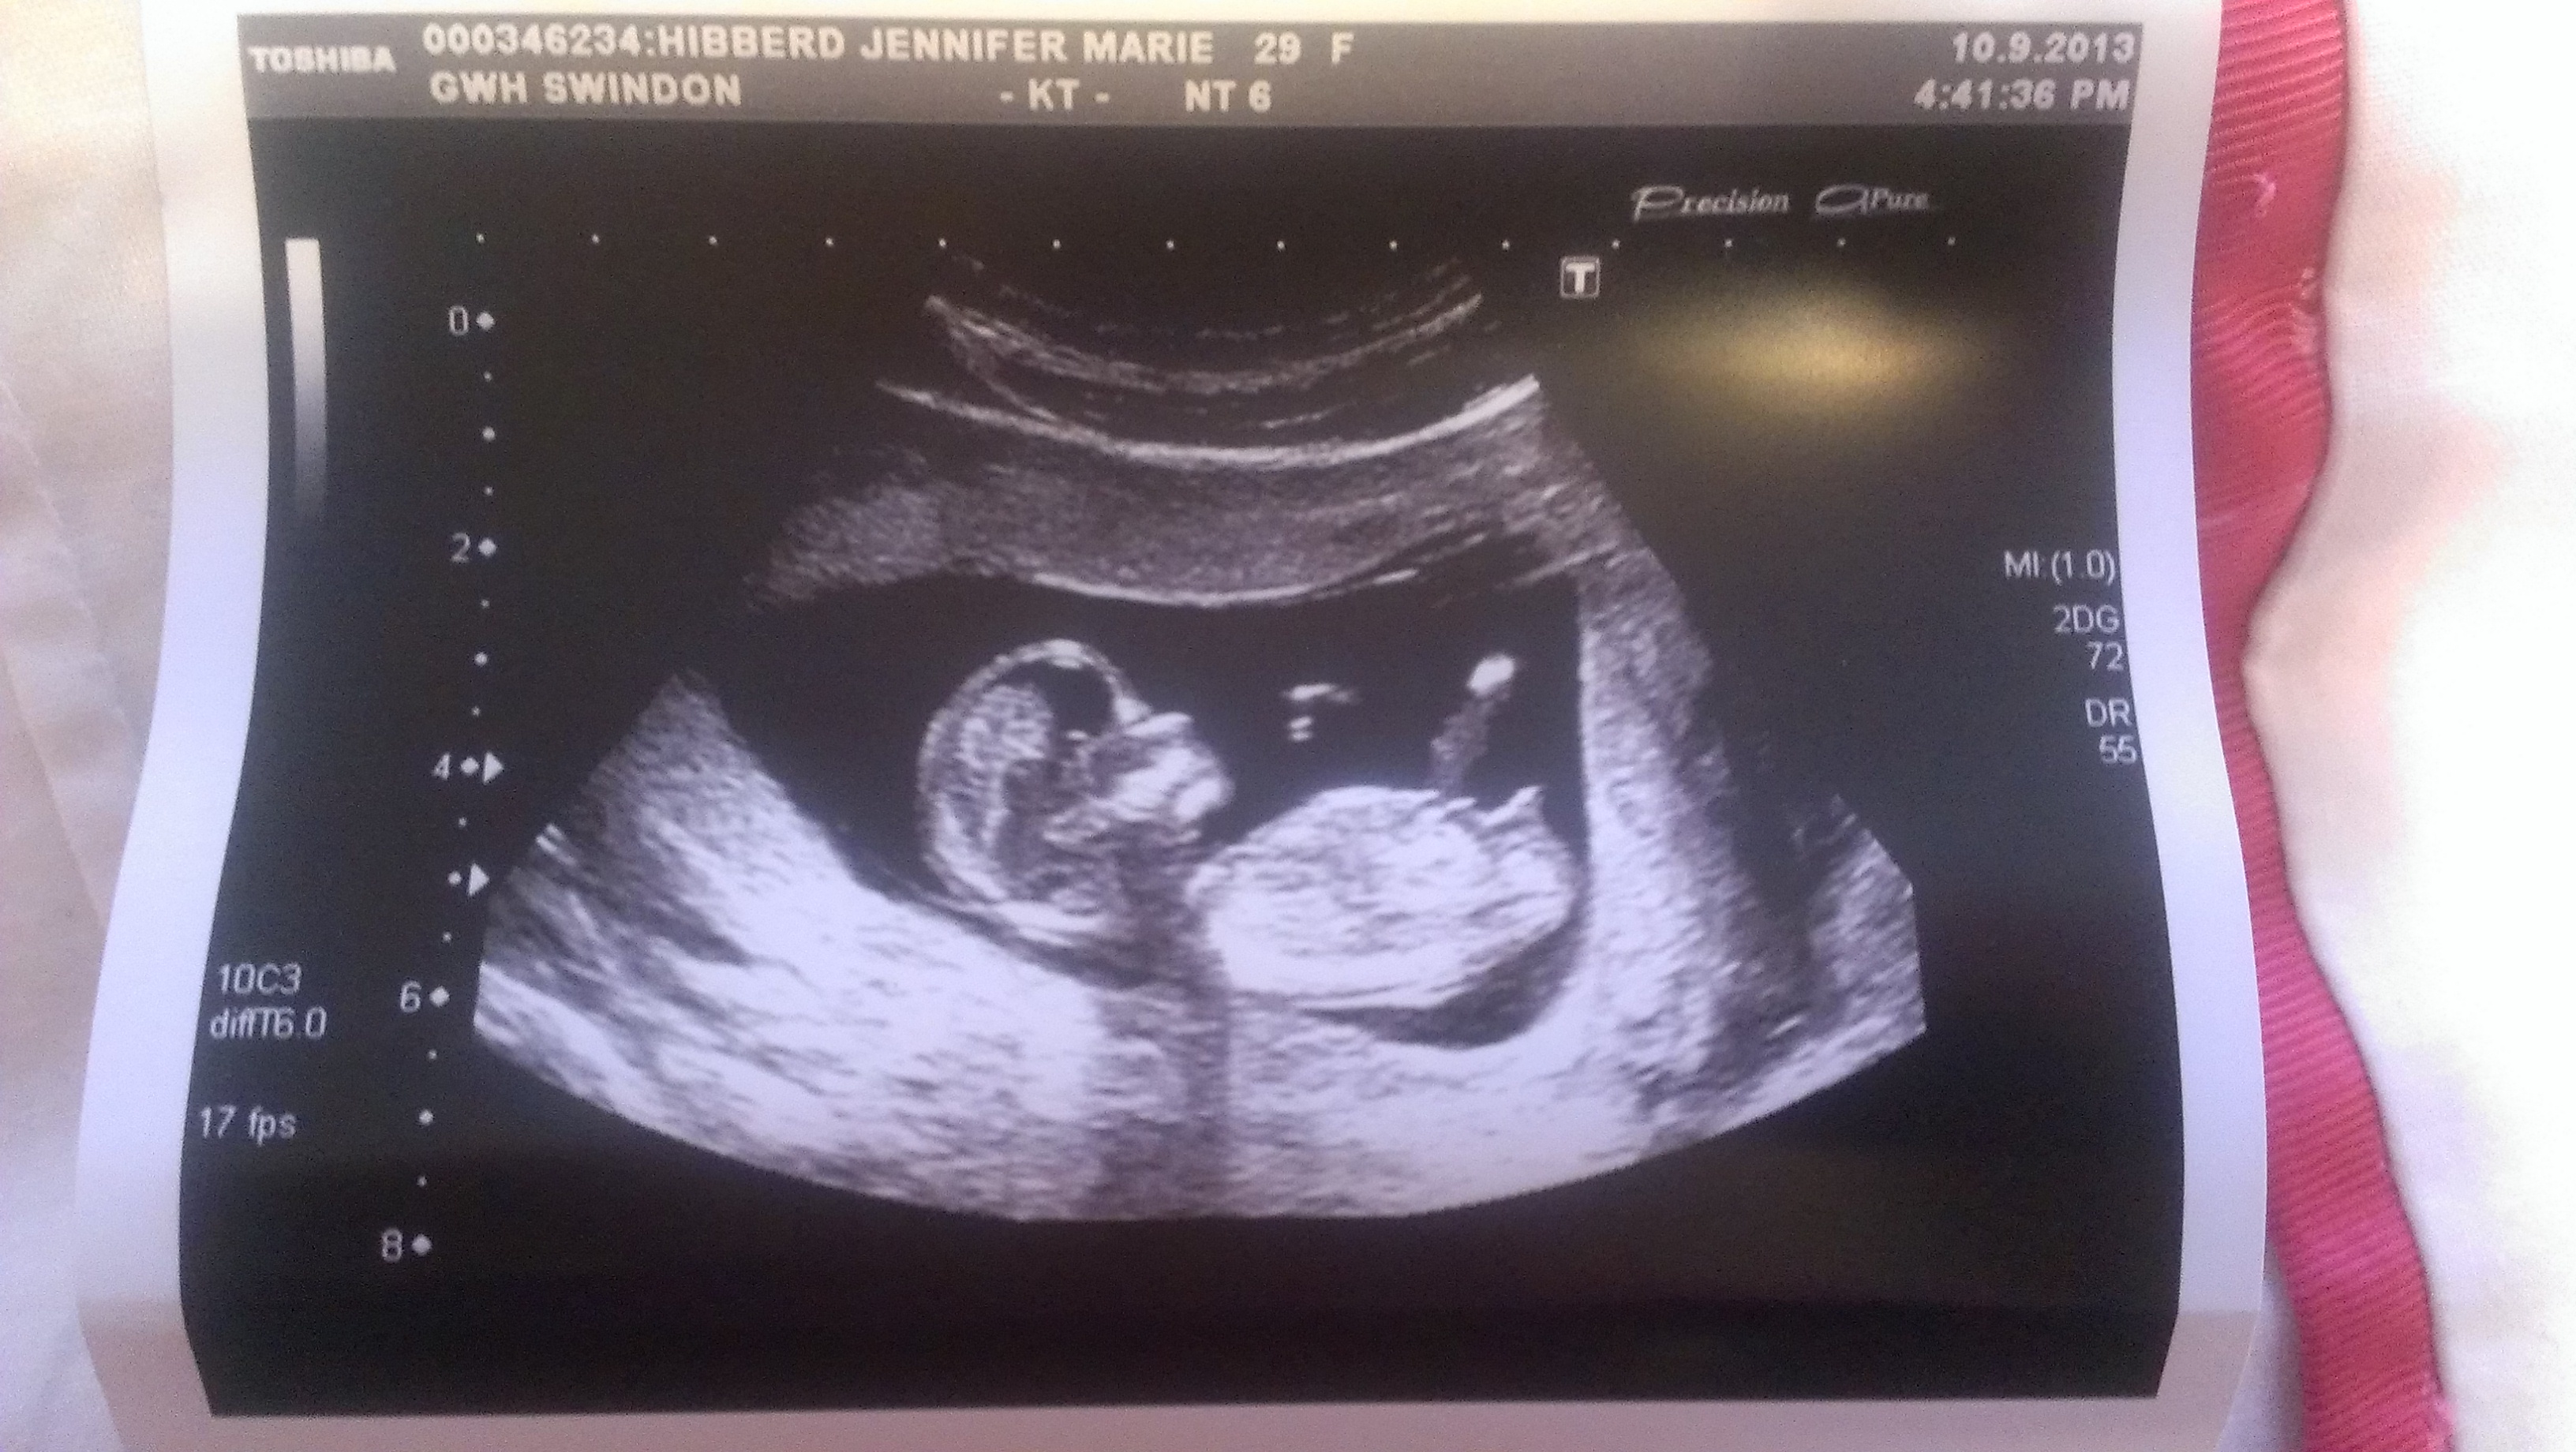

Attachment 14007Attachment 14008

I'm new to this forum so hello! I've read about the nub theory online and wondered if any experienced eyes would have a guess at my baby's gender looking at my scan pics! I hope I've attached the pics correctly.